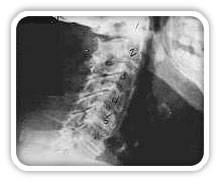

Phase Two Subluxation Degeneration

Phase two subluxation degeneration is normally seen in subluxations that have been present between 20 and 40 years. This phase has some of the same characteristics of the previous phase including a loss of normal curvature and position as well as an alteration in segmental motion. In addition, spines with Phase Two Subluxation Degeneration many times show a reduction in the patient's range of motion in that area. X-rays of a phase two begin to show calcium changes or buildup at certain levels of the spine. These changes are sometimes called by many names including spurs and arthritis. Disc spaces between the affected vertebrae are noticeably narrower and may appear to be flattening out. Although most people with Phase Two Subluxation Degeneration may not exhibit any symptoms, some may start to feel stiff or achy. Chiropractic reconstructive care for patients in phase two ranges from 1.5 years to 2.5 years. Again, if Phase Two Subluxation Degeneration is left uncorrected it slowly advances to the next phase.